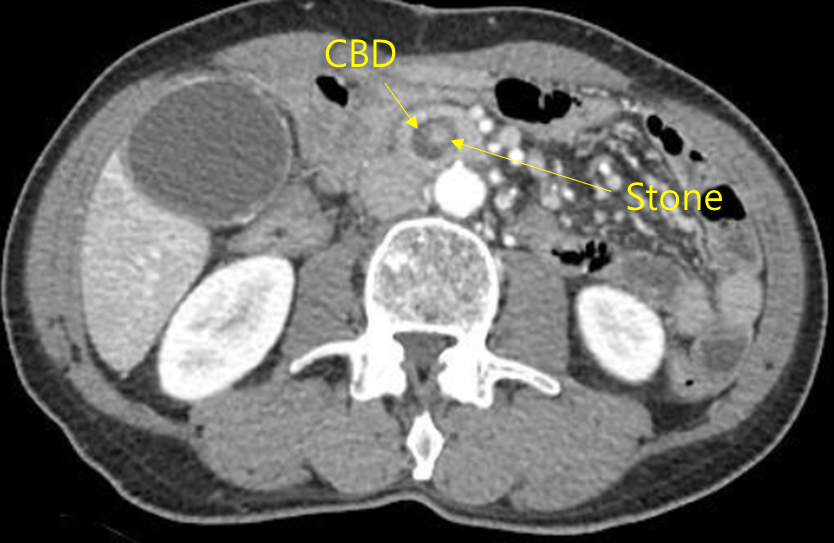

Img | CT: CBD dilatation MRCP: CBD filling defect with proximal CBD dilatation |

발열, 황달, 우상복부 통증을 호소하는 환자에게서 담도폐쇄의 혈액검사 소견과 영상검사 소견이 관찰되므로 총담관담석으로 인한 급성 담관염으로 진단할 수 있다.

• 이를 확인하기 위한 CT에서 CBD dilatation이 보이며, MRCP에서는 CBD stone으로 추정되는 filling defect가 관찰되며 그 defect보다 proximal하게 bile duct dilatation이 보인다.